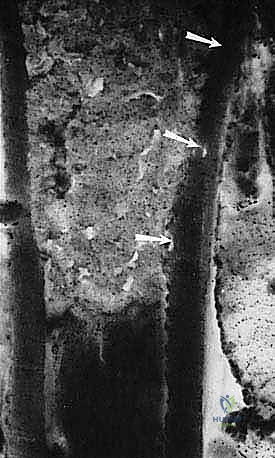

* الساركوما العظمية (Osteosarcoma): الأكثر شيوعاً، تظهر عادة حول الركبة (أسفل الفخذ أو أعلى القصبة).

تتميز هذه الأورام بقدرتها على اختراق الأنسجة المجاورة وتكوين ما يُعرف بـ "المنطقة التفاعلية" (Reactive Zone) أو الكبسولة الكاذبة، والتي تحتوي غالباً على خلايا سرطانية مجهرية. هذا المفهوم البيولوجي هو ما يوجه الدكتور محمد هطيف في تحديد مدى الاستئصال الجراحي.